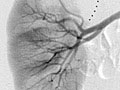

Angiografía de una masa renal